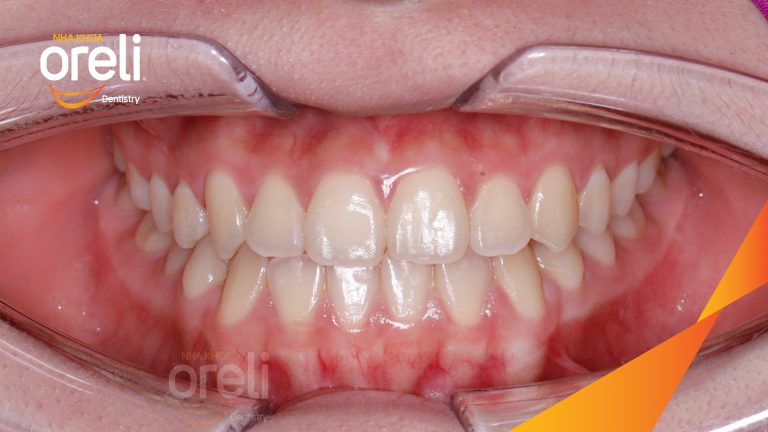

Ca niềng chỉnh chen chúc sai khớp cắn hạng 3 móm nhẹ – Kết quả thực tế ở Oreli Niềng răngChen chúcMóm Xem thêm